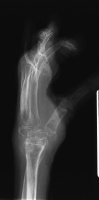

Her left index and middle fingers are grossly unstable.

Xrays show radiocarpal collapse, proximal migration of the proximal phalanges, flail PIP joints and loss of the proximal half of the dorsal cortex of the proximal phalanges.